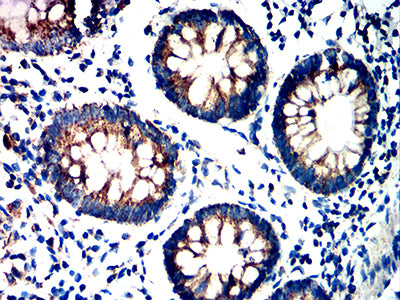

分类: 科研抗体货号: 32228别名: CLEC2; CLEC2B; PRO1384; QDED721; 1810061I13Rik应用: IHC,FCM反应种属: Human